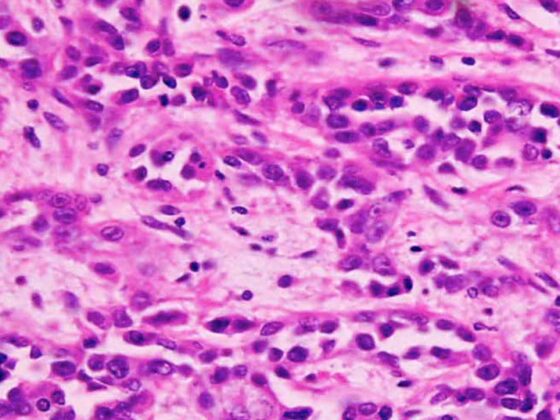

Der Begriff der künstlichen Intelligenz stammt aus den 50er-Jahren des 20. Jahrhunderts und umfasst eine Ansammlung von Technologien, welche einem Computer erlauben, typische Eigenschaften der menschlichen Intelligenz zu emulieren. Anfänglich wurden grosse Hoffnungen in diese Technologien gesetzt und früh wurde versucht, diese in der Medizin zu etablieren. Zu Beginn des 21. Jahrhunderts war es aufgrund der anfänglich ernüchternden Ergebnisse eher still in der Erforschung der KI in der Medizin. Mehrere wichtige Entwicklungen ebneten jedoch den Weg zum Durchbruch der Technologie.